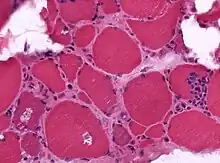

A muscle biopsy from someone who is diagnosed with myositis.

Muscle biopsies are the most reliable tests for diagnosing myositis.[4]